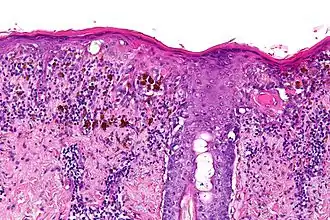

L'aspect anatomo-pathologique est pour la composante intradermique celui d'une prolifération lentigineuse longeant les annexes pilo-sébacées, dont la densité et les atypies augmentent en fonction de l'ancienneté. Des thèques et une ascension pagétoïde peuvent apparaître. Quand vient la composante dermique l'aspect est celui d'un nodule fusocellulaire avec mitoses peu nombreuses[6].